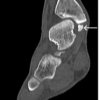

The second case involved a 76-year-old female patient. She had been treated for hypopharynx (stage Ⅳ T2N2bM0) cancer 20 years ago, using radiation and chemotherapy. She had received 60 Gy radiations to the pharynx and 46 Gy to the right supraclavicular fossa, followed by a planned right neck dissection. No recurrence has been observed during the follow-up. However, she began to have neck pain 20 years after the radiotherapy. Within a few days, she developed bilateral upper extremity paresis (3 according to the MMT), paresthesia, and gait disorder. A blood examination showed a leukocyte count of 7700/mg and a CRP level of 9.87 mg/dL; an elevated inflammatory response was observed. Destruction of the C4–5 intervertebral disc and expansion of the retropharyngeal space were shown in radiography (Fig. 2a). CT scanning showed destruction of the C5 and C6 vertebrae (Fig. 2b). Sagittal STIR MRI showed destruction of the C5–6 intervertebral disc, signal intensity changes of the C4–C7 vertebrae, a retropharyngeal abscess, and an epidural abscess causing spinal cord compression (Fig. 2c). A fiberscope showed redness and edema of the pharyngeal mucosa secondary to radiotherapy (Fig. 2d). A puncture of the retropharyngeal abscess was performed through the neck using ultrasound. Streptococcus dysgalactiae was isolated in culture. The patient was diagnosed with spondylodiscitis at levels C4–C7 due to ORN. Cervical posterior decompression and fusion (C2–Th2) were performed on the day of admission. Surgical screw insertion for fixation was performed via three incisions at both the C2-3 and bilateral C7-T1 sites. An ILS was inserted on the left side of C2, and a PS was inserted on the right side of C2, while a PVFS was inserted on the left side of C3, and another PS was inserted on the right side. A PS of C3 was inserted through another 2-cm lateral incision on the left side. For the cervical-thoracic region, PS were bilaterally inserted into T1 and T2, and a rod was then passed under the muscle and connected to the screw heads. As the infected vertebral body at C4–7 was not suitable for direct PS placement, caudal fixation was carried out in T1 and T2. In addition, a C5–6 laminectomy was performed through an incision separate from that for the fusion (Fig. 2f). After surgery, the patient remained intubated and underwent a tracheostomy because of the difficulty of reintubation due to a retropharyngeal abscess and the risk of laryngeal edema after extubation. She was treated with a 6-week course of intravenous antibiotics (SBT/ABPC) and a 19-week course of oral antibiotics (AMPC and CVA). The infection was controlled, and the retropharyngeal abscess improved. The tracheotomy cannula was removed after one month. Postoperatively, bilateral upper extremity paresis, paresthesia, and gait disorder improved. To date, 10 months after surgery, the patient’s neurological condition is stable.